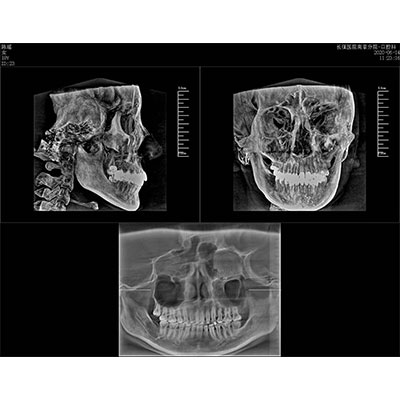

該款牙科CBCT產(chǎn)品采用動態(tài)平板探測器,獲得三維圖像的同時還具有數(shù)字化全景功能,廣泛應用于口腔頜面外科、正畸科、正頜外科、種植科、牙體科、顳下頜關節(jié)科等術前術后。

專有三維重建算法,可提供任意位置高清斷層影像。

通過三維容積影像,提取高清口腔全景影像。

可同時觀察軸向面、冠狀面和矢狀面圖像,方便臨床診斷。